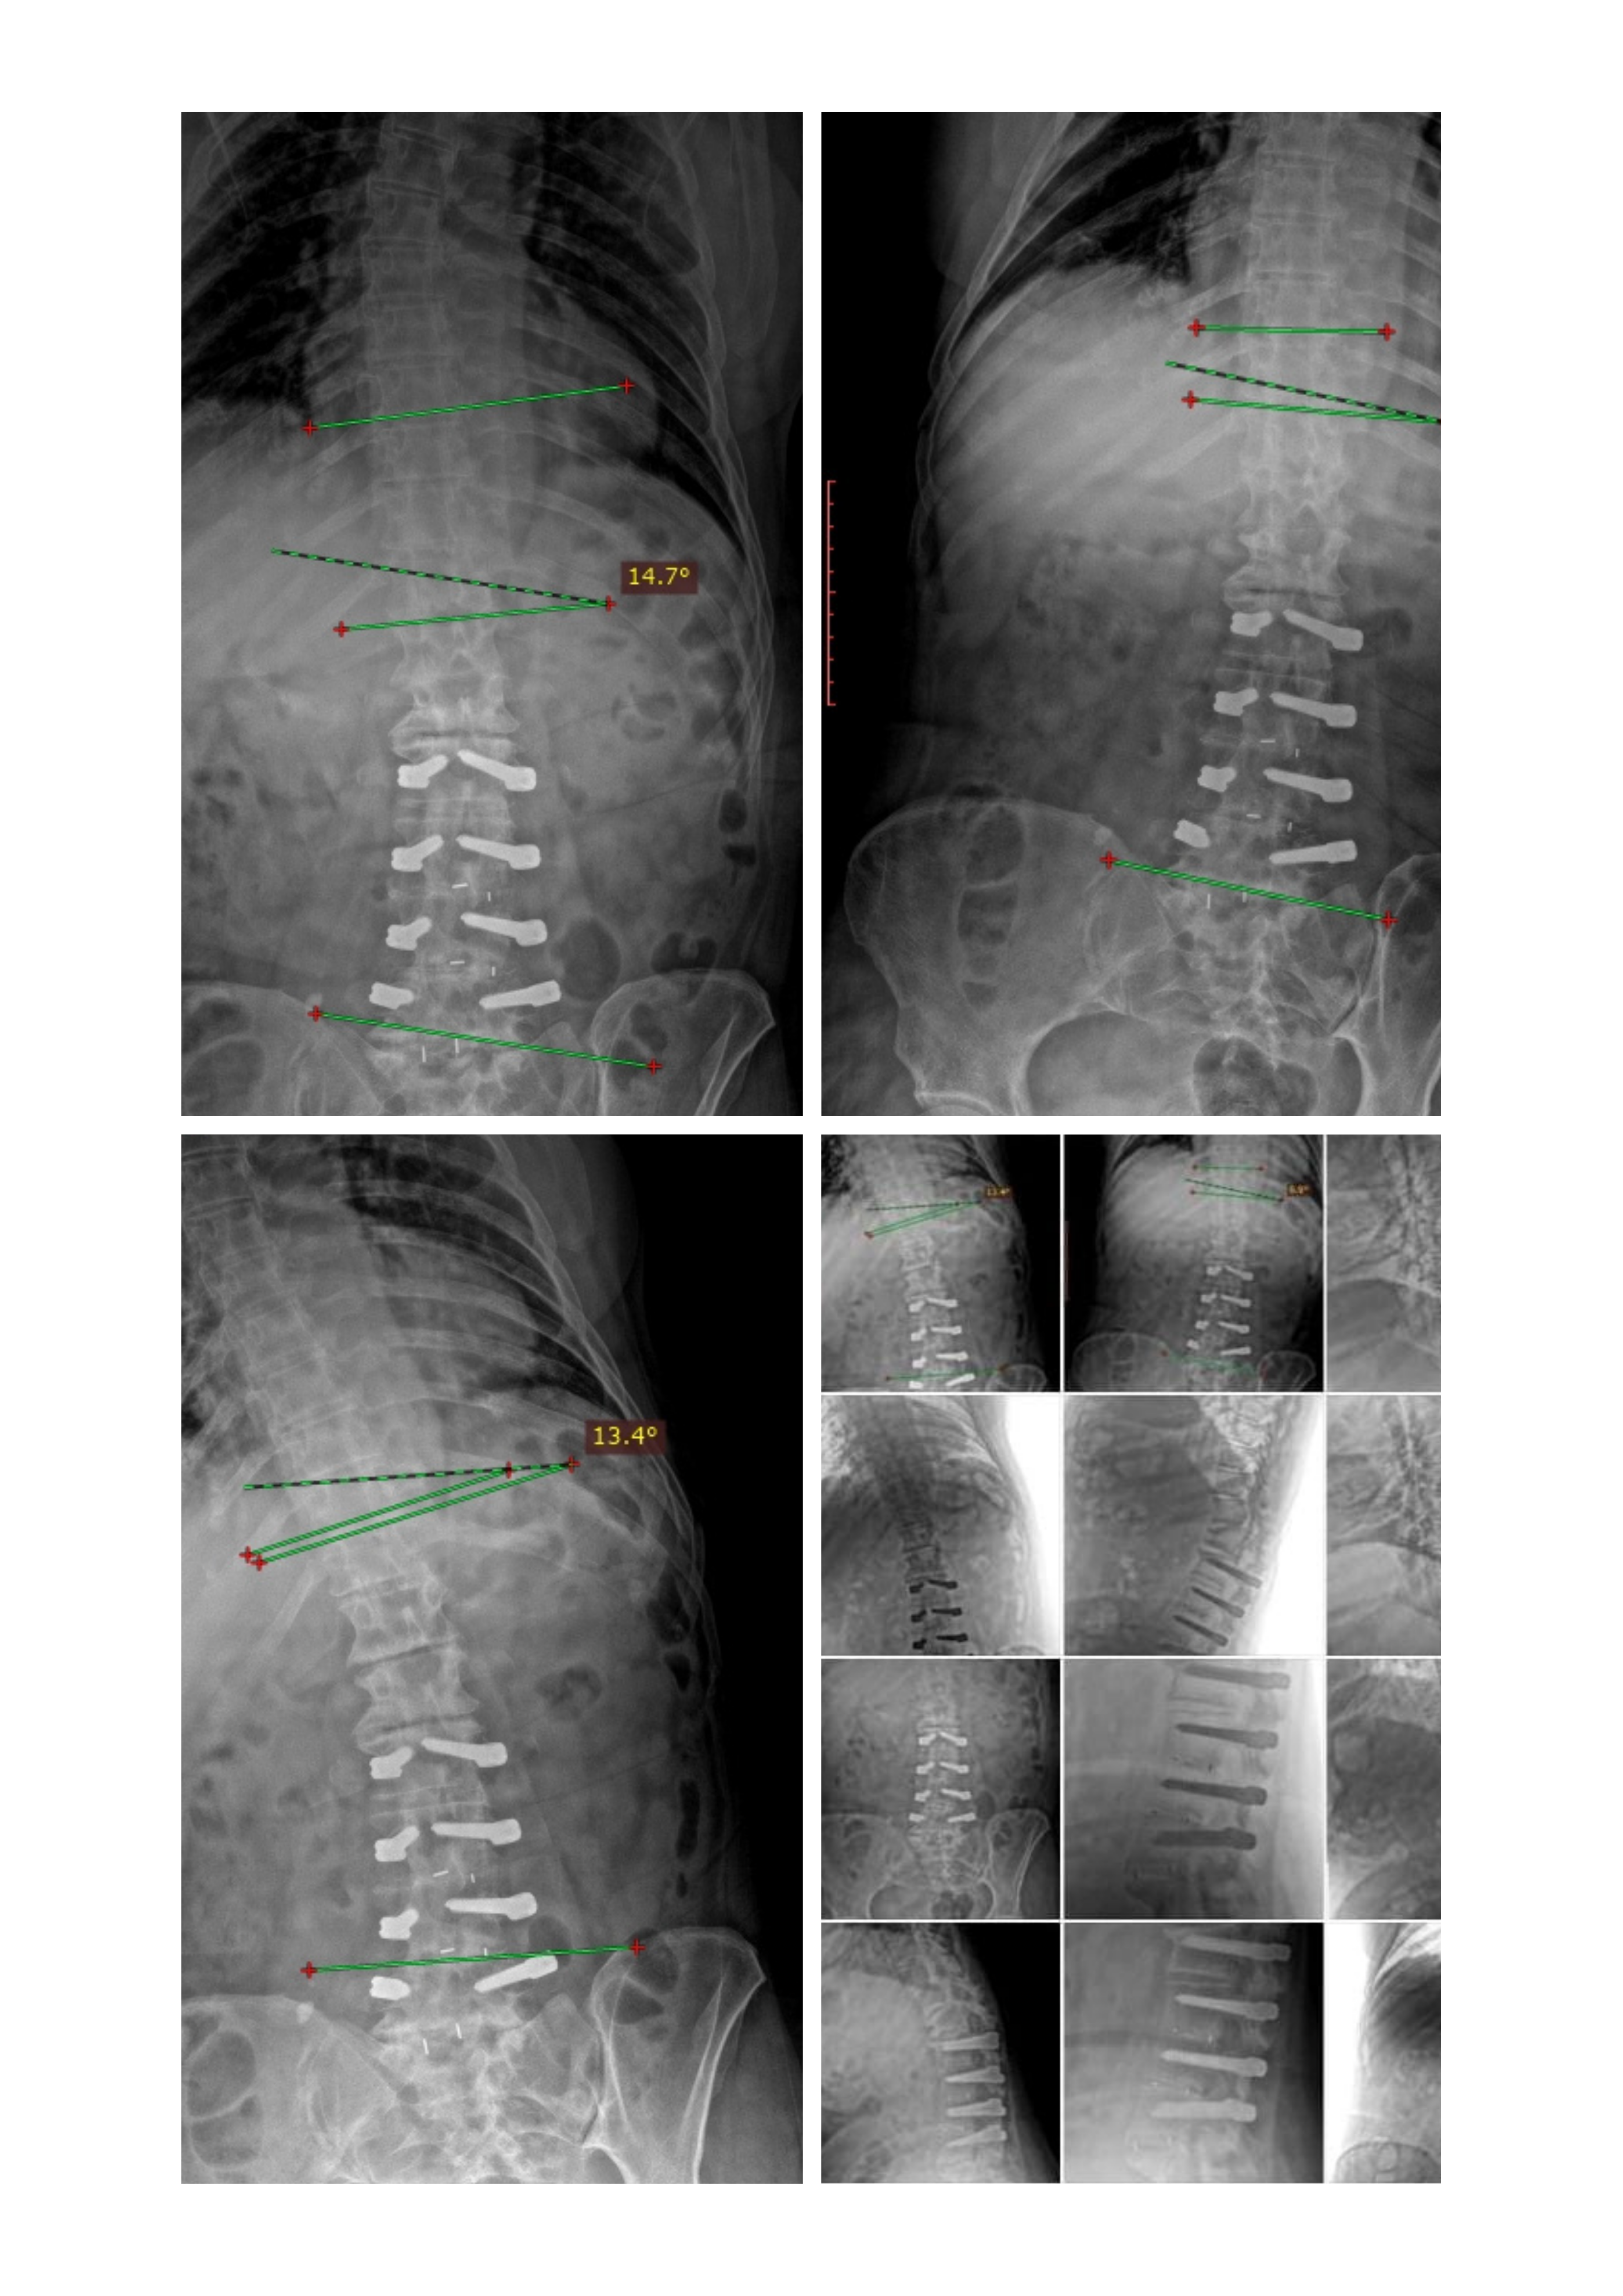

Desde hace más de 12 años, Mirna sufre un problema grave y progresivo de columna. En 2013 fue sometida a una cirugía que no resolvió el problema y el dolor nunca desapareció. Con los años, su condición ha empeorado.

Camina inclinada hacia adelante debido al desplazamiento de vértebras

No puede mantenerse derecha ni de pie por mucho tiempo